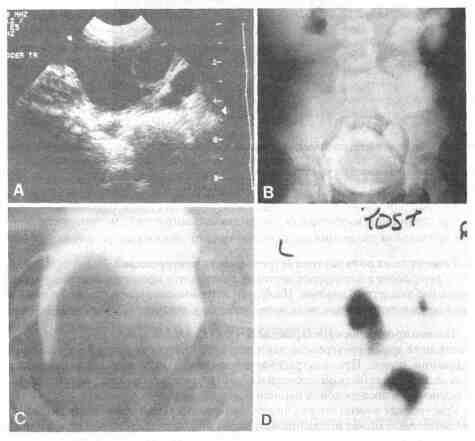

почек для определения функции верхних мочевых путей

Рис. 41-2. А. Ультразвуковое исследование, при котором определяется большое уретероцеле в мочевом пузыре В. Внутривенная урограмма, на которой определяется большое уретероцеле в мочевом пузыре а также функционирующий нижний полюс почки и расширенный мочеточник С Цистограмма, на которой определяется большое уретероцеле D Почечная сцинтиграмма на которой определяется гидронефротическая трансформация нижнего полюса и отсутствие функции верхнего полюса, отток из которого происходит через эктопическое уретероцеле в мочевой пузырь 7. Какой метод лечения предпочтительнее при уретероцеле в одинарной системе (ортотопическом уретероцеле)? Несмотря на то, что существует риск развития пузырно-мочеточникового рефлюкса, первичным этапом лечения является простое эндоскопическое рассечение уретероцеле. Если развивается рефлюкс и почка нуждается в сохранении, можно выполнить реимплантацию мочеточника. 8. Перечислите возможные лечебные мероприятия при эктопическом уретероцеле. 1. Эндоскопическое рассечение уретероцеле. 2. Резекция верхнего полюса почки и, возможно, уретерэктомия. 3. Пиело-пиелостомия в верхнем полюсе при функционирующих почках. 4. Резекция верхнего полюса почки с тотальной уретерэктомией и восстановлением целостности мочевого пузыря. 9. Какова функциональная активность верхнего полюса при эктопическом уретероцеле? Верхний полюс при эктопическом уретероцеле обычно функционирует плохо или вообще не функционирует. Во многих случаях сегмент может иметь неправильное развитие. Однако в некоторых случаях в нем имеется функционирующая ткань, которую следует сохранить. 10. Развивается ли рефлюкс при уретероцеле? Рефлюкс может развиться в 50 % мочеточников, в которых имеется уретероцеле. Он может быть обусловлен слабостью мышечного слоя и растяжением мочевого пузыря эктопическим мочеточником. Рефлюкс также может наблюдаться в контрлатеральном мочеточнике, возможно, вследствие растяжения треугольника. 11. Может ли рефлюкс спонтанно прекратиться? Незначительный рефлюкс на стороне поражения и в контрлатеральном мочеточнике может спонтанно прекратиться. Однако рефлюкс более высокой степени обычно не прекращается и требует хирургической реимплантации. 12. Могут ли уретероцеле быть двухсторонними? Да. Билатеральные уретероцеле могут наблюдаться в 10 % от всех случаев эктопических уретероцеле. 13. Что такое цекоуретероцеле? Цекоуретероцеле — это уретероцеле, которое распространяется субуретрально в проксимальный или даже дистальный отдел мочеиспускательного канала. Избранная литература Balchick R.J.,Nasrallah P. F. Cecoureterocele.J. Urol., 137:100, 1987. Blyth В., Passerini-Glazel G., Camuffo C., et al. Endoscopic incision of ureteroceles: Intravesical versus ectopic. J. Urol., 149: 556, 1993. Caldamone A. A., Snyder H. M., Duckett J. W. Ureteroceles in children. Follow-up of management with upper tract approach. J. Urol., 131:1130,1984. Churchill B. M., Sheldon C. A., McLone G. A. The ectopic ureterocele. A proposed practical classification based on renal unit jeopardy. J. Pediatr. Surg., 27:497,1992. Decter R. M., Roth D. R., Gonzales E. T. Individualized treatment of ureterocele. J. Urol., 142: 535, 1989. Gonzales E. T. Anomalies of the renal pelvis and ureter. In: Kelalis P. P., King L. R., and Belraan A. B. (eds). Clinical Pediatric Urology, 3rd ed. Philadelphia, W. B. Saunders, 1992. King L. R., Koglowski J. M., Schacht M. J. Ureteroceles in children. A simplified and successful approach to management. JAMA, 249: 1461, 1983. Retik A. B. Ectopic ureter and ureterocele. In: Walsh P. C., Gittes R. E., Perlmutter A. D., Stamey T. A. (eds). Campbell's Urology. Philadelphia, W. B. Saunders, 1986. Rich M. A., Keating M. A., Snyder H. M., Duckett J. W. Low transurethral incision of single system intravesical ureteroceles in children. J. Urol., 144: 120, 1990. Stephens F. D. Congenital Malformations of the Urinary Tract. New York, Praeger, 1983, pp 320-322,329. Tank E. S. Expenence with endoscopic incision